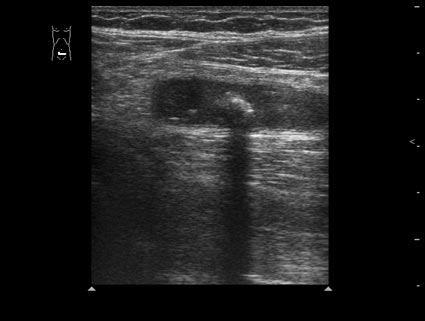

Пациент 32 лет.

В правой подвздошной области определяется утолщенный аппендикс, не компрессируется при надавливании датчиком, в просвете определяется аппендиколит; окружающие аппендикс ткани инфильтрированы.